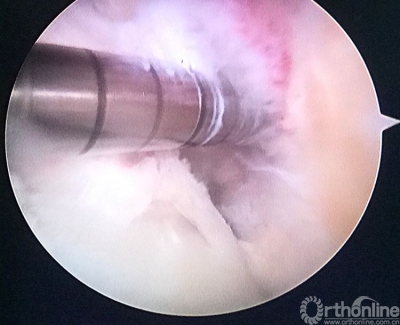

用由小到大的空心钻头钻股骨隧道,观察隧道情况,至8mm时隧道内骨面90%达新鲜化。

股骨隧道内取出的原重建肌腱及袢,糜烂。

己经完成的股骨隧道,改用强生横穿钉固定。